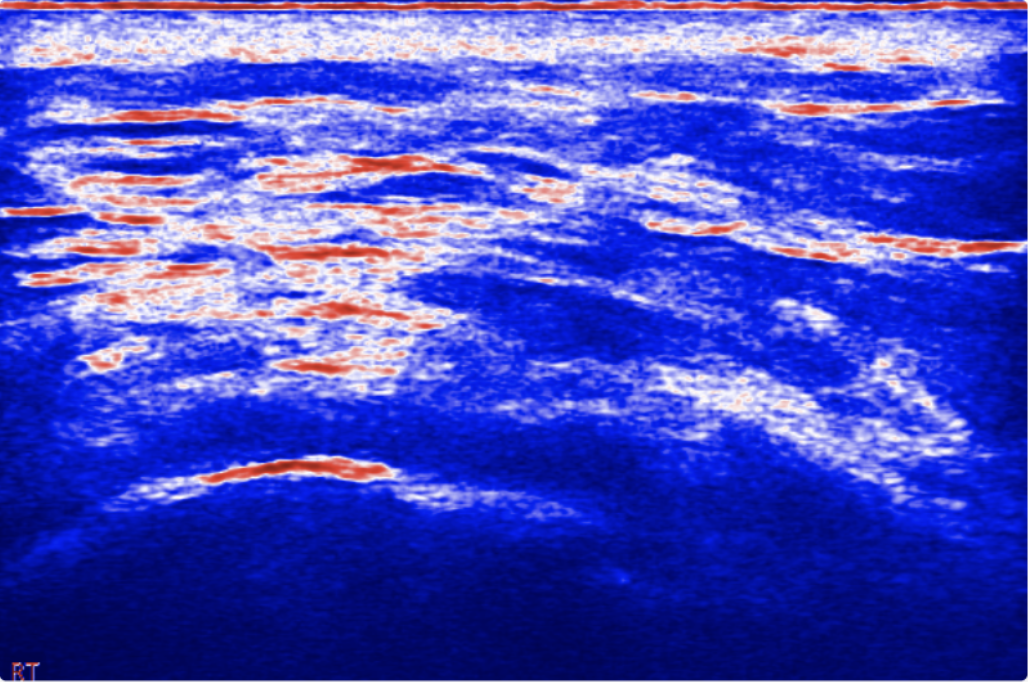

Pliability Analysis

Blue = soft tissue, Red = stiff tissue

Pliability Score™ represents the tissue fluidity. The higher the score, the more soft tissue is found. Conversely, the lower the score, the more hard tissue is found.

Irregularities may be indicative of disorganized, calcified or adhered soft tissue.

Color Coding Guide

RED becomes darker where more hard tissue is found•BLUE becomes darker where more soft tissue is found